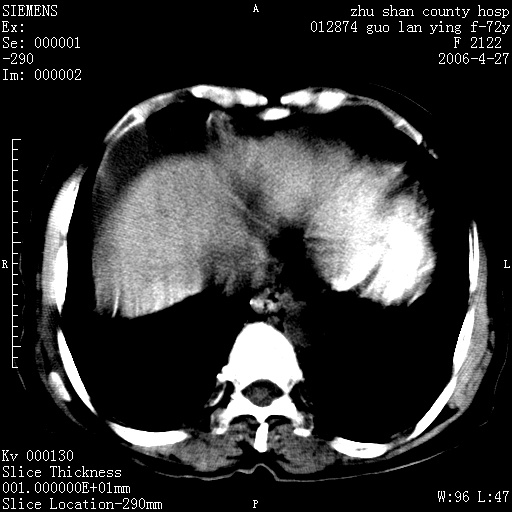

病人 女性 72岁 b超要求ct检查!

平扫所见:胆囊区两点壮高密度影,灶周有伪影{请问楼主患者有手术病史?}。肝实质内未见明显异常{建议强化或mri}.腹腔有少量积液,脾明显增大.右肾形态似不规则?

腹腔内示积液征,脾脏略增大,肝脏由于运动伪影较多,影响观察,内未见明显高密度区,胆囊内示两处高密度结石。胃窦部壁轻度增厚。另外,肝脏的前缘似有游历气体。不知病人的临床如何?有必要做胃的检查,还有,看看骨窗是否有腹腔游离气体还是肠管影响的。

如果b超对肝脏有怀疑,肝脏的增强扫描还是尽量去做。

肝脏缩小,脾脏增大,肝脾外缘及胆囊窝液性密度影,肝脾ct值正常,胆囊区见两个类圆形高密度影,下腔静脉前方类圆形软组织密度影为肝脏岛叶,胃幽门区见软组织密度影,十二指肠钡剂充盈不好.

1:腹水2:胆囊结石3肝硬化?(不确定,请结合临床)4幽门区占位?(建议胃肠透视)

肝硬化,脾大,少量腹水

肝硬化、脾肿大,腹水,胆囊区高密度影(结石或异物),是否有外伤史

肝硬化、腹水、脾大,胆囊结石可以肯定。只是肝右叶两个低密度有必要增强确定一下;排除小肝癌。

谢谢牟教授在百忙之中还认真的点评我的帖子!也谢谢大家的鼎力相助,此病人是我们医院护理部主任的母亲!病人以前无特别不舒适!昨天b超后发现有问题!做ct的目的在于排除肝内占位性病变,此病人以前无手术外伤史.